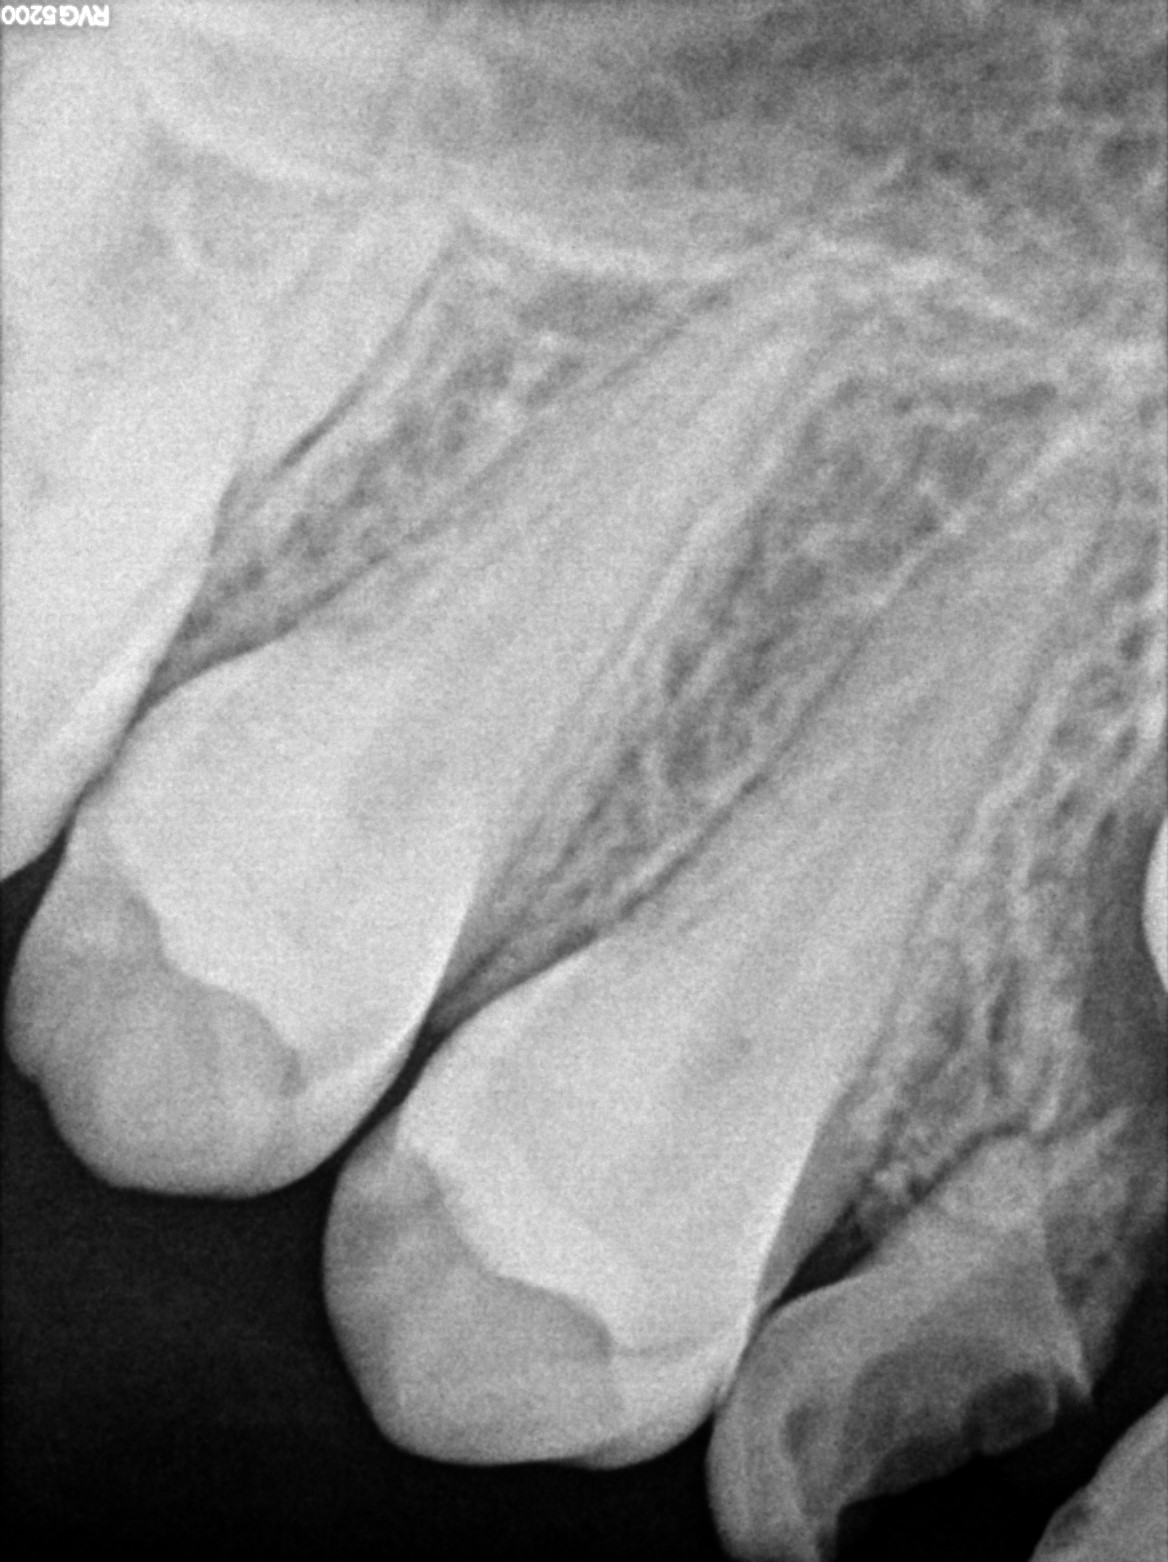

Dental Radiographs FHIR: DocumentReference · LOINC 24641-7

R5.3.jpg

24641-7